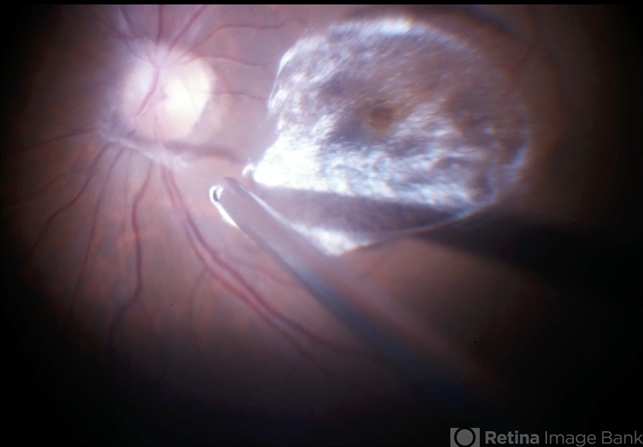

- triamcinolone, PVD induction

- Intraoperative view of Triamcinolone-assisted posterior vitreous detachment.